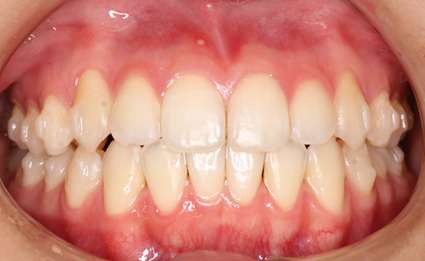

マウスピース矯正は、専用の透明なマウスピースを使用する矯正方法です。この方法の最大の特長は、装置が目立たないことです。透明な素材で作られているため、装着していてもほとんど見えず、日常生活で他人に矯正をしていることを気づかれる心配がありません。見た目を気にせず、自然な笑顔を保ちながら治療が進められます。

さらに、マウスピースは、必要に応じて簡単に取り外すことができます。食事の際にはマウスピースを外して好きなものを自由に楽しむことができ、矯正中の食生活に制限がかかる心配がありません。また、歯磨きやマウスピースの洗浄も簡単に行えるため、口腔内を清潔に保ちやすく、虫歯や歯周病のリスクを減らすことができます。

マウスピースは、患者さん一人ひとりの歯並びに合わせてカスタマイズされており、快適な装着感を提供します。治療は、段階的に新しいマウスピースを使用して歯を少しずつ移動させるので、痛みも比較的少ないです。